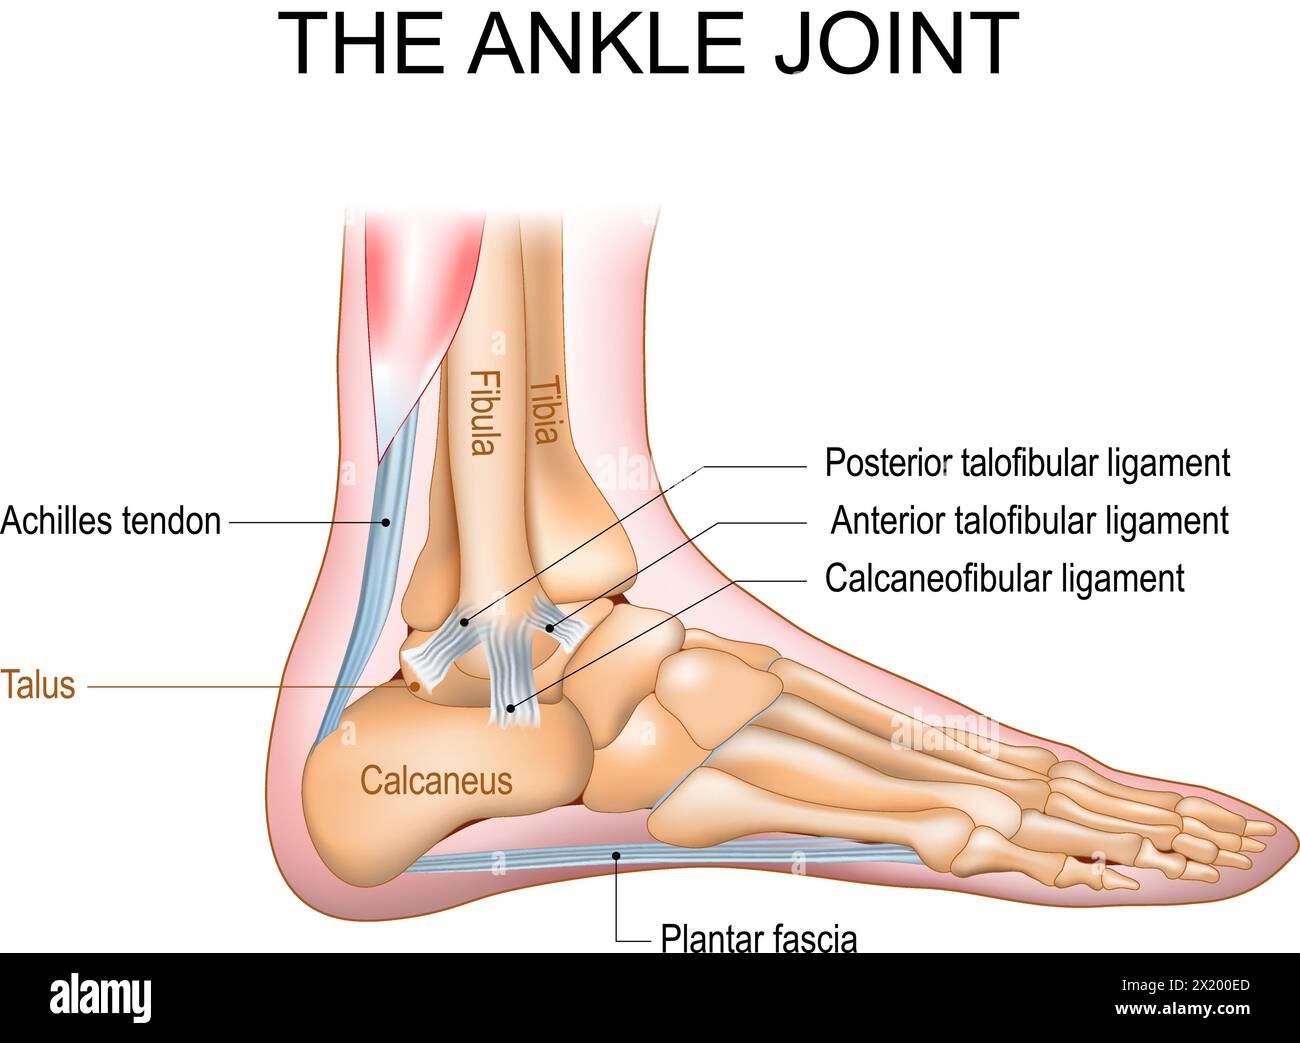

RF2X200ED–L'anatomie de l'articulation de la cheville. Région talocrurale ou os sauteur. Partie du corps humain où le pied et la jambe se rencontrent. Fascia plantaire et tendon d'Achille